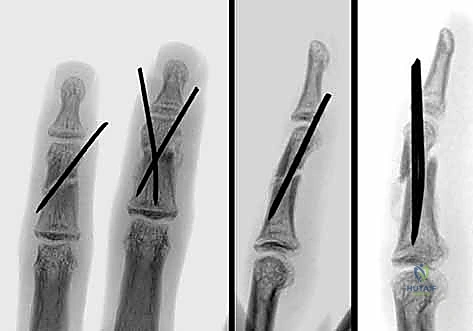

1. الرد المغلق والتثبيت بأسلاك كيرشنر (CRPP - Closed Reduction and Percutaneous Pinning):

تُعد هذه الطريقة الأقل توغلاً. يقوم الدكتور هطيف برد الكسر يدوياً تحت توجيه جهاز الأشعة السينية المباشر (C-arm) في غرفة العمليات، ثم يقوم بإدخال أسلاك معدنية دقيقة (K-wires) عبر الجلد لتثبيت العظم.

* المزايا: لا تتطلب شقاً جراحياً كبيراً، تحافظ على الإمداد الدموي للعظم، وتقلل من خطر التصاقات الأوتار.

* العيوب: تتطلب إبقاء جزء من السلك خارج الجلد (عادةً)، مما يستلزم إزالتها في العيادة بعد 4-6 أسابيع.